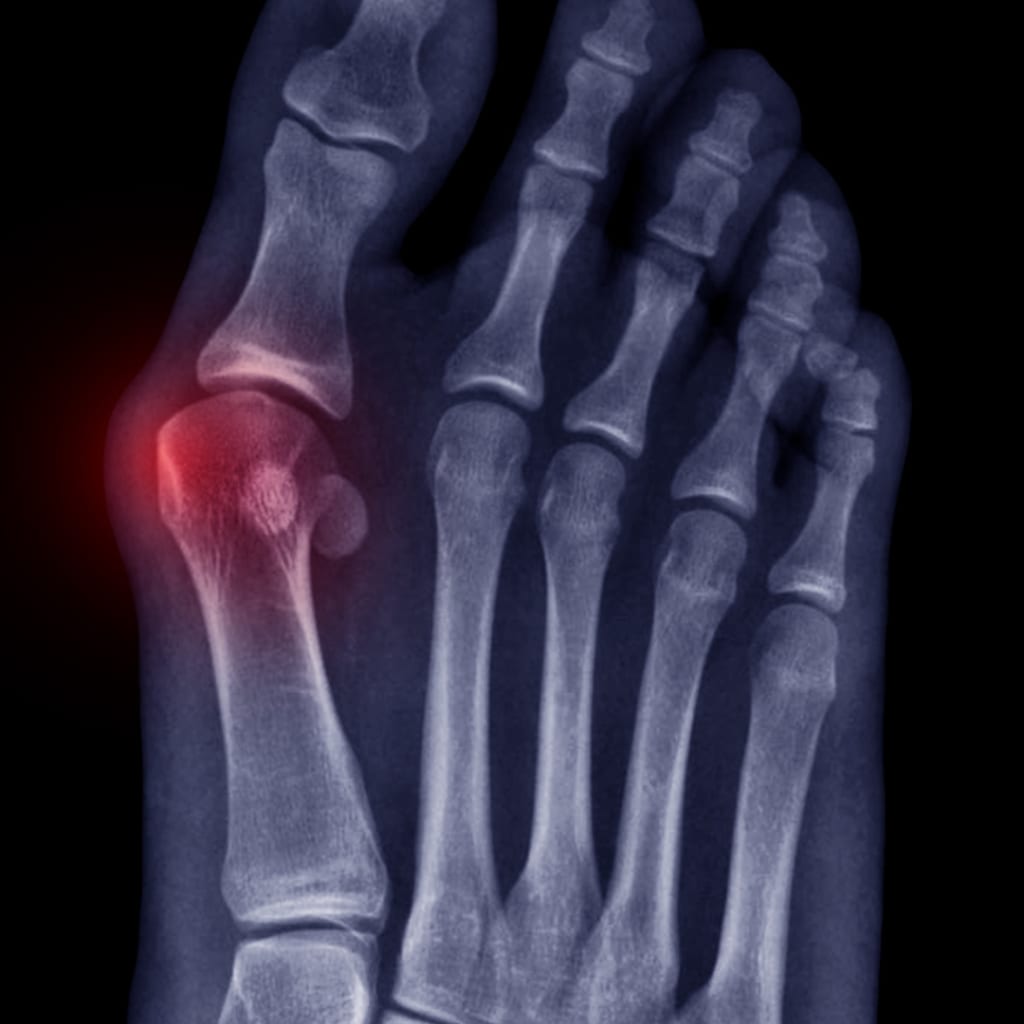

How to Melt Bunions

A bunion is a bony bump that occurs at the joint of the big toe. It occurs when proper mechanics aren’t practiced, most notably when the ankle is collapsed (pronated), and the foot moves into external rotation (toes positioned away from midline, like a duck). This causes the tip of your big toe to get pulled…